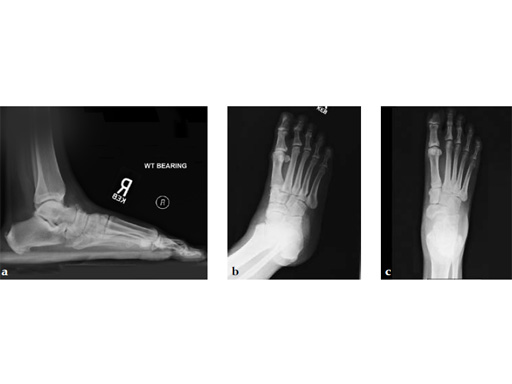

Case 4: First TMT fusion plate

A 60-year-old woman with pes plano abductovalgus (flatfoot deformity).

Case provided by Andrew Sands, New York, New York, USA

The patient was treated by headless compression screw 6.5 tuber osteotomy, TMT plantarflexing osteotomy, and first TMT fusion a plate.